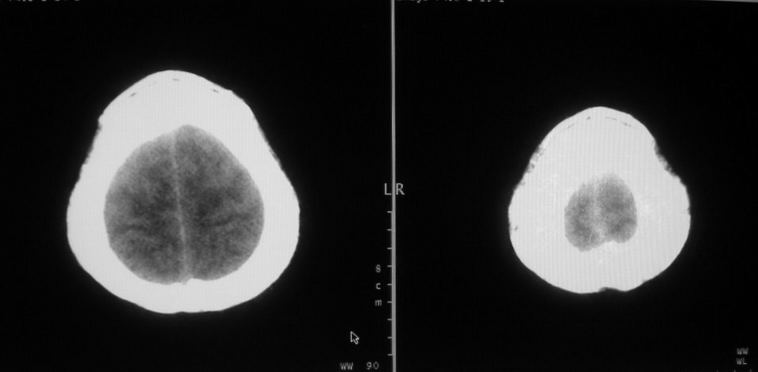

女,44岁,头痛数月。

图像质量不能明确诊断。

囊性脑膜瘤

肿瘤建议增强